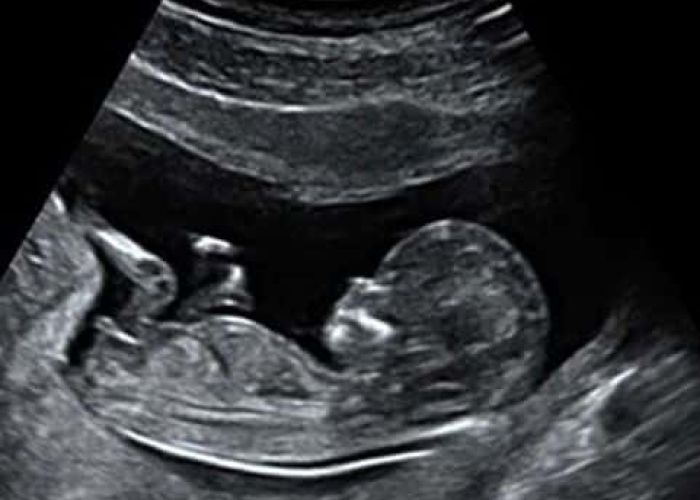

Vi tilbyder ultralydsscanninger

Ultralyd er lydbølger med så høj frekvens, at de ikke kan høres af det menneskelige øre. Man kan heller ikke mærke lydbølgerne. Lydbølgerne reflekteres af det væv de rammer og ved hjælp af avanceret udstyr dannes et billede på skærmen. Ultralydsscanning af gravide har været anvendt siden midten af 1960´erne og der er aldrig fundet tegn på skadelige virkninger – hverken hos fostret eller den gravide.

Du har mulighed for at læse meget mere om de scanninger vi tilbyder i 2D og 3D/4D scanning her på hjemmesiden. Hos Den lille jordemoder er det essentielt, at alle føler sig velkomne og trygge. Derfor er der afsat god tid til alle scanninger, således der er tid til at svare på de spørgsmål i eventuelt har om barnet eller graviditeten generelt.